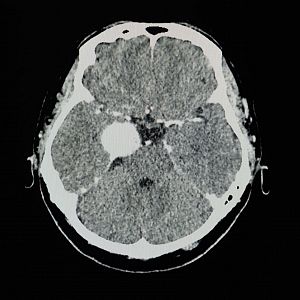

Imagen de las pruebas médicas para preservar el rendimiento del paciente en el ajedrez EUROPA PRESS

Un aficionado al ajedrez se enfrenta a la necesidad de extirpar un tumor en el lóbulo parietal izquierdo, pero manifiesta un claro deseo: no dejar de ser un maestro en el tablero. Los profesionales médicos aceptan el reto. Gracias al protocolo, que combina el mapeo de estimulación eléctrica, mientras el paciente se encuentra despierto, con la resonancia magnética funcional, los investigadores han logrado identificar y preservar las áreas del cerebro involucradas en las habilidades necesarias para jugar al ajedrez.

Antes de la cirugía, se han evaluado diversos procesos cognitivos del paciente relacionados con el juego, como la búsqueda visual, que implica localizar las piezas en el tablero, la recuperación de reglas, donde se determina la legalidad de un movimiento, y la capacidad de anticipar el jaque mate. A través de la combinación de técnicas, los investigadores identifican un punto crucial en la circunvolución supramarginal izquierda, fundamental para mantener la competencia ajedrecística.